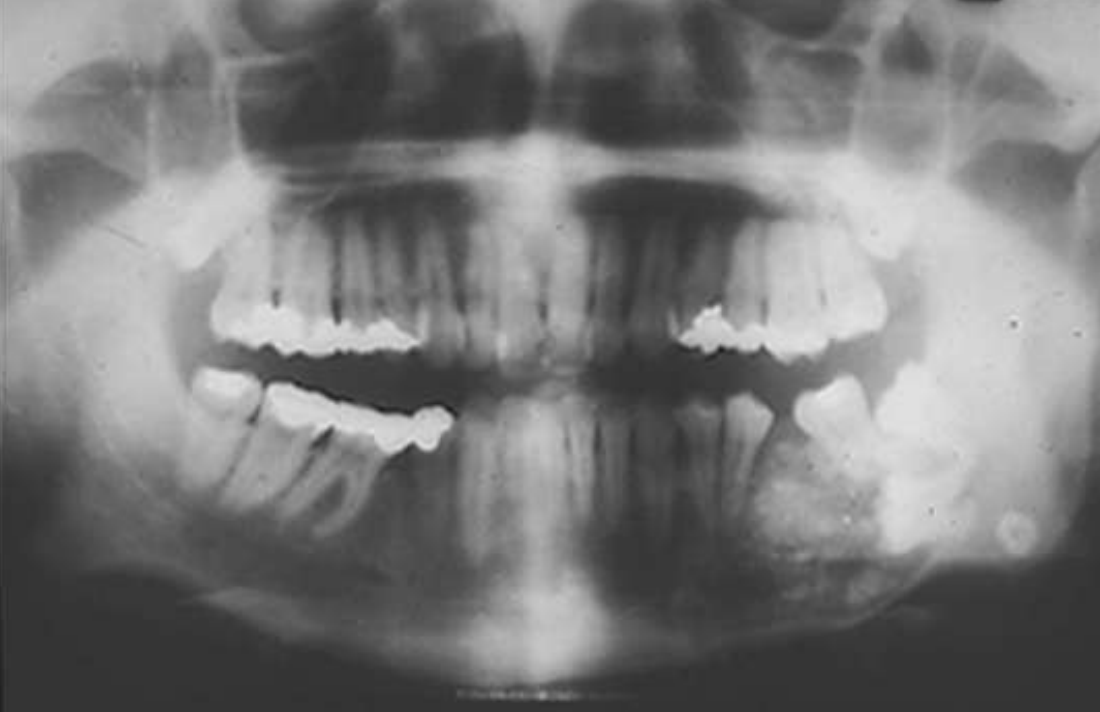

ameloblastoma

Multilocular

Root resorption

Thinning of inferior mandibular border

Septae appear coarse

Displacement of teeth

Displacement of inferior alveolar nerve canal